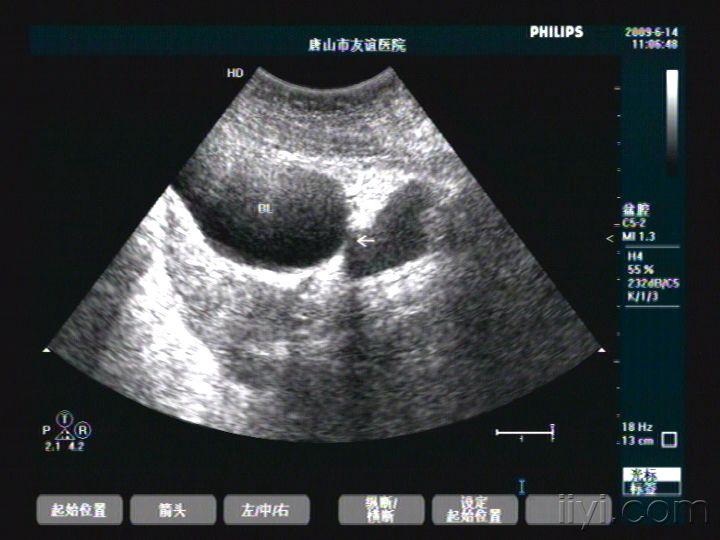

膀胱憩室一例,希望大家喜欢 - 超声医学讨论版 - 爱爱医医学论坛

图片尺寸640x480